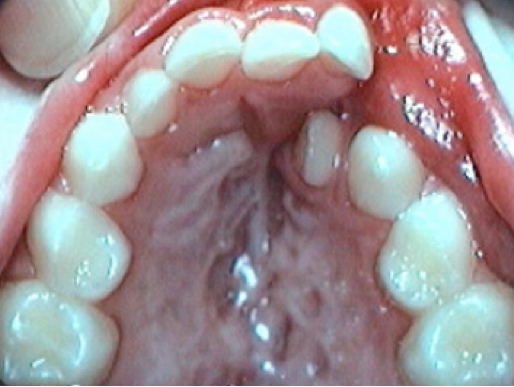

3) Dental malpositions:

Fig 4 Dental malpositions : rotations, crossbite, lack of space